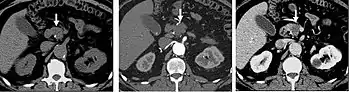

FIGURE 4: Arterial and portal venous phase CT of cholangiocarcinoma. Selected images from a biphasic CT demonstrating early arterial enhancement of a posterior right hepatic lobe mass with mild wash out on delayed phase images in the setting of cirrhosis characteristic of hepatocellular carcinoma.

The late arterial phase is timed to correspond to the peak concentration of contrast material in highly vascular tumors and is performed approximately 20–35 seconds after the injection of intravenous contrast. Early arterial phase imaging is predominantly utilized for angiography and will be discussed separately. Late arterial phase imaging is almost always performed in conjunction with other phases (e.g. portal venous phase) to allow more complete characterization of any identified abnormalities (figure 4). The primary indication for a late arterial phase is for the evaluation of hypervascular tumors of the liver such as hepatocellular carcinoma or hypervascular metastases (figure 4). Typical hypervascular tumors for which this would be used include: hepatocellular carcinoma; renal cell carcinoma; melanoma; carcinoid/neuroendocrine tumors; some sarcomas; choriocarcinoma; and thyroid carcinoma. Although a “hypervascular”, biphasic evaluation would generally be used for these patients, note that a single phase is often adequate for follow up imaging.

FIGURE 6. Selected images from a biphasic CT of Focal Nodular Hyperplasia in the left hepatic lobe (arrow). These masses have characteristic early arterial enhancement (6a) with contrast wash out on the portal venous phase images (6b) from the mass making these lesions difficult to identify on portal venous phase images alone.

When evaluating hepatic masses, it can be advantageous to have both late arterial and portal venous phase images (biphasic imaging, figure 4) since some tumors enhance briskly during the arterial phase (hepatocellular carcinoma, hepatic adenoma, follicular nodular hyperplasia (FNH), and hypervascular metastasis), but may be occult or difficult to characterize on portal venous phase imaging alone (figure 6). However, it should be stressed that the addition of late arterial phase images is only indicated if one of these tumors is suspected, or if there is a need for further characterization of a hepatic mass, since the large majority of patients will not benefit from the addition of this phase. In addition, if there is a need to definitively characterize a hepatic mass, MRI is generally more sensitive and specific, with no associated radiation dose.